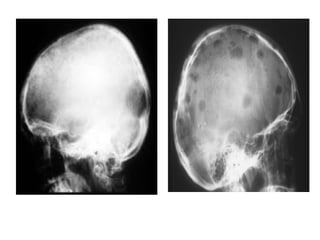

MODEL OF HEAD OF A PATIENT WITH

TERTIARY SYPHILIS

MODEL OF HEADOF A PATIENT WITH TERTIARY SYPHILIS